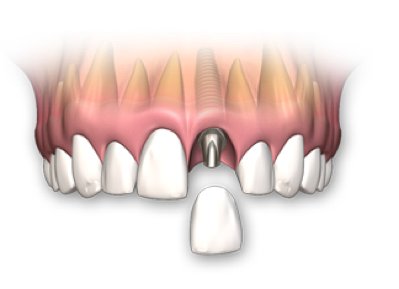

¿Cómo funciona un implante?

Reemplazamos la pieza dental original por una fabricada en Titanio biocompatible que se introduce en el hueso de la mandíbula, sobre ésta nueva raíz se fija una pieza de metal y cerámica (corona) resistente que se iguala en color y forma con el fin de brindar un aspecto lo más natural posible.

Se trata de un proceso sencillo e indoloro que le permitirá recuperar toda la funcionalidad de estética y de masticación.

- (Si le falta un diente)

- Implante fabricado en Titanio Grado V de la más alta pureza.

- Reemplaza la raíz del diente y evita la perdida de hueso.

- Indicado para adultos y tercera edad.

- Respaldo casa de implantes SIN